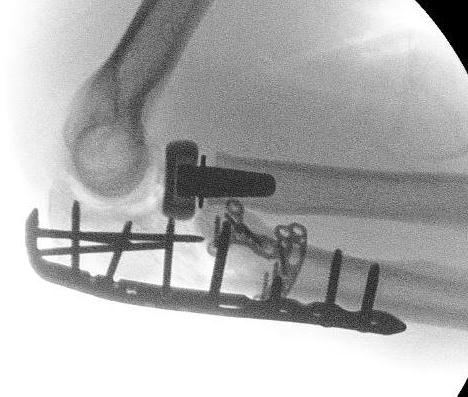

coronoidCoronoid Buttress Plate AP

Medial approach and buttress plate with LCL repair

buttress plate